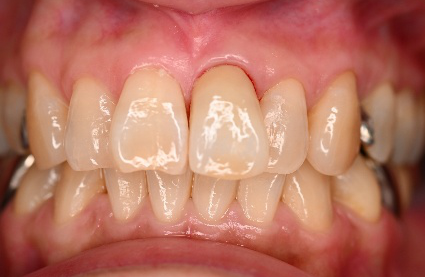

女性Aさん 50代(オールセラミック冠)

主訴

色が変わった上前歯をきれいにしたい。

治療内容

根管治療をし、オールセラミック冠を被せました。

所感

神経が取り除かれ、大きく詰め物がされていました。詰め物及び歯自体が変色し、虫歯になっていました。根管治療をし、ファイバーコアを入れ、オールセラミック冠を被せました。自分の歯は、捻転していましたが、被せ物により歯並びを改善することができました。

オールセラミック冠1本:¥104,500(税込)

Before

After